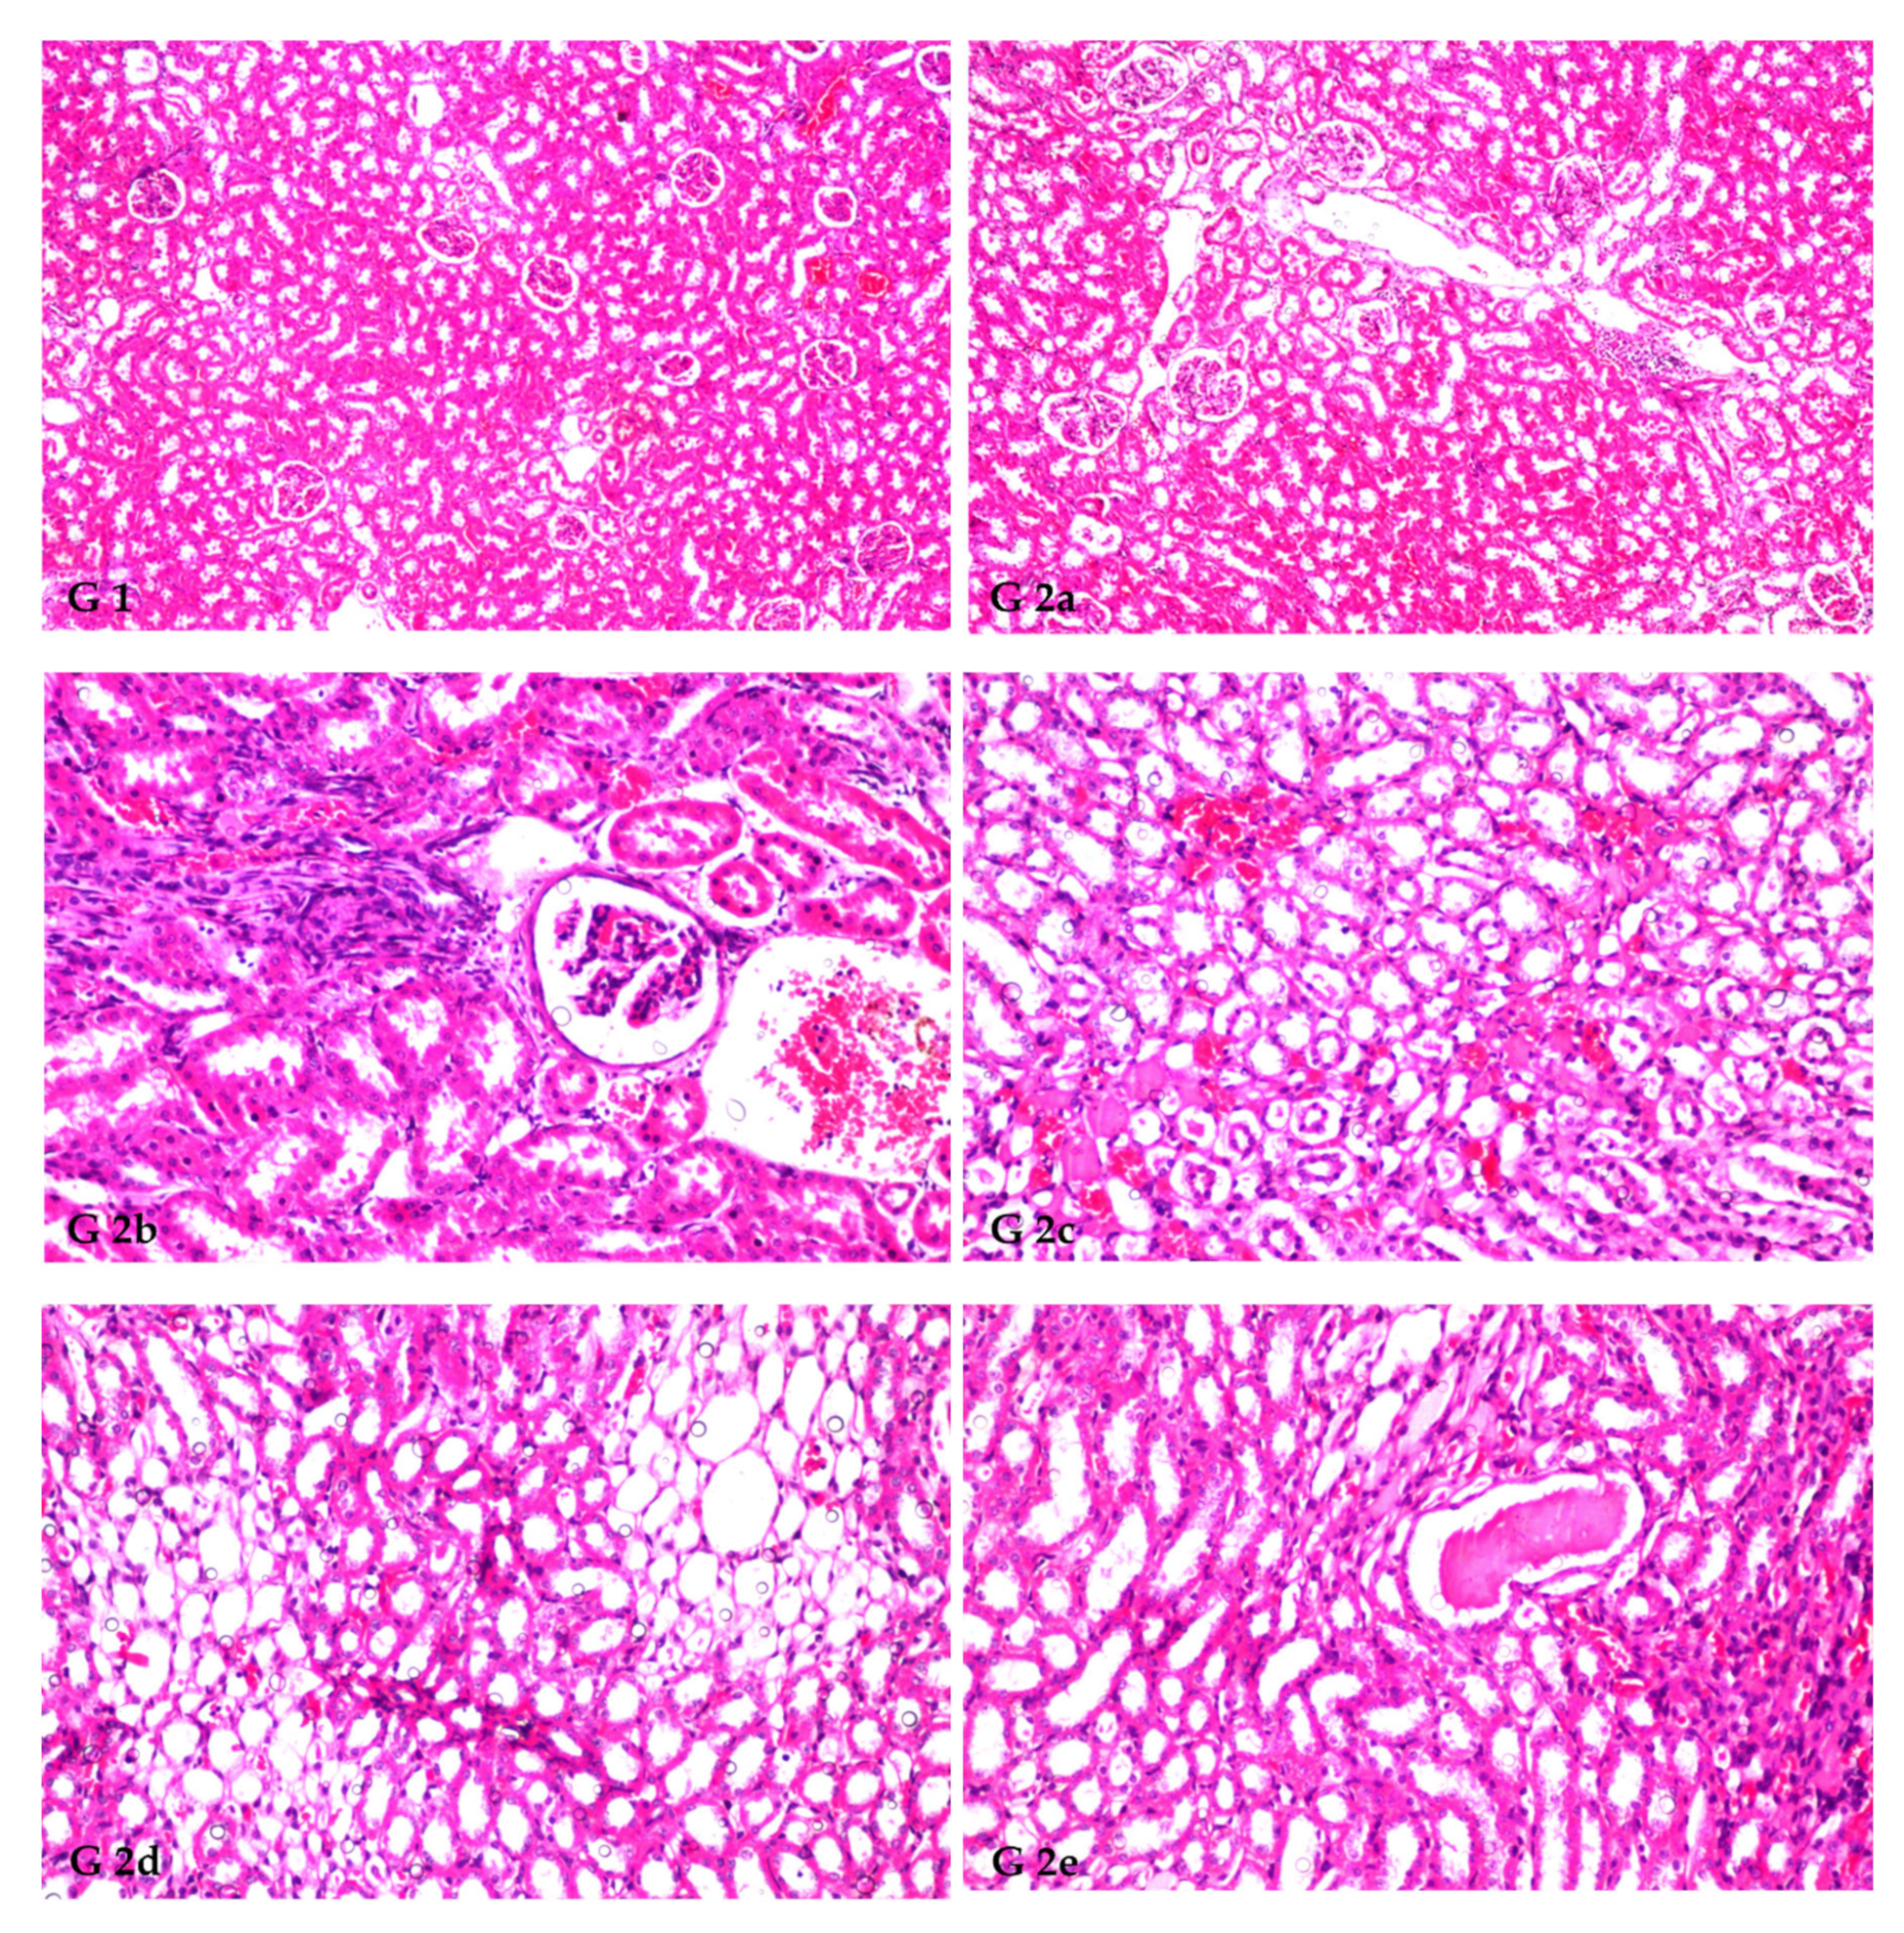

The histopathology confirmed the biochemical findings, as currently remarked. Figure 1 demonstrates the histological alterations in rat kidneys of treated rats treated with FS and FSS extracts. In this study, the kidneys of the control group (GI) had normal glomeruli and tubules at the cortex (Figure 1, G1). The histoarchitecture of the CCl4-treated rats (G2) showed focal inflammatory cell infiltration at the cortex surrounding the glomeruli and blood vessels and between the tubules (Figure 1, G2a). There was also focal fibrosis with atrophy and obliteration of the tubules with dilatation of the blood vessels at the cortex (Figure 1, G2b). The corticomedullary portion showed focal hemorrhages between the obliterated tubules (Figure 1, G2c) and focal cystic dilatation with flattened lining epithelium in others (Figure 1, G2d). Eosinophilic cast formation was detected in the lumen of the cystic tubules at the corticomedullary adjacent to the focal fibrosis (Figure 1, G2e). In G3, when 300 mg kg−1 aqueous extract of FS was given, congestion was observed in the cortical blood vessels (Figure 1, G3). However, administrating 600 mg kg−1 FS aqueous extract (G4) and both 300 and 600 mg kg−1 FSS alcoholic extract, as marked in (G5 and G6), respectively, showed no histopathological alteration as recorded in (Figure 1, G4, G5, and G6).

Figure 1.

Histopathological findings in rat kidneys treated by FS and FSS extracts along with CCl4 nephrotoxicity induction (X16 and X40). GI: Show normal histological structure of the glomeruli and tubules at the cortex, as recorded (G1). The histoarchitecture of the CCl4-treated rats (G2) showed focal inflammatory cell infiltration at the cortex surrounding the glomeruli and blood vessels as well as between the tubules (G2a), focal fibrosis with atrophy and obliteration of the tubules with dilatation of the blood vessels at the cortex (G2b), corticomedullary portion showed focal hemorrhages between the obliterated tubules (G2c), focal cystic dilatation with flattened lining epithelium in others (G2d), and eosinophilic casts formation was detected in the lumen of the cystic tubules at the corticomedullary adjacent to the focal fibrosis (G2e). G3 (300 mg kg−1 aqueous extract of FS) shows congestion in the cortical blood vessels (G3). In (G4) (600 mg kg−1 FS of aqueous extract), (G5, 300 mg kg−1 of FSS alcoholic extract), and (G6, 600 mg kg−1 of FSS alcoholic extract) showed no histopathological alteration as recorded in (G4, G5, and G6), respectively.

Histopathological kidney findings are congruent with biochemical estimates. CCl4 injection (G2) induced inflammation around glomeruli, blood arteries, and tubules. Dogukan et al. [113] observed similar histopathological alterations in the renal tissue of rats in response to CCl4. Histological alterations may also be produced by functional overloading of nephrons, leading to renal failure [86] and/or free radical production via CCl4 metabolism [114,115]. FS and FSS extracts help restore the kidney from the destructive effects of CCl4. This may be due to FS and FSS (as potent antioxidants) acting on reactive oxygen species (ROS) induced by CCl4 [116]. The phenolic components in F. vulgare extracts have an antioxidative role and free radical scavenging properties, which allows them to reduce CCl4-induced acute nephrotoxicity [52]. Our results are consistent with other researchers who found that plant extracts with varying molecular compositions have pharmacological effects by restoring normalcy after CCl4 abuses were introduced [52,117].